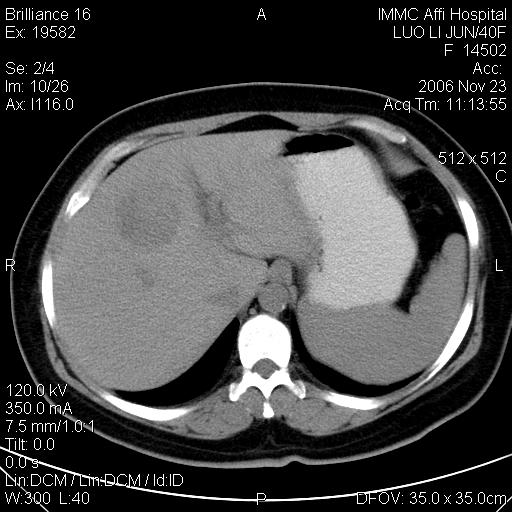

标题: CT5664:我也发一个肝脏的片子大家看看

很典型的肝癌。

典型肝癌

肝癌

速升速降,典型肝癌.

典型肝癌.

是啊,典型的早出早归!

快进快出典型肝癌.

符合肝癌的增强特征。支持肝癌!

病灶好圆!可能恶性度不高。

不能除外肝细胞腺瘤吧,还是得结合病史。

很好的片子,可惜增强做的比较失败,a期时间没有把我好,实际到了静脉早期了,否则会更典型。

最终考虑是肝腺瘤